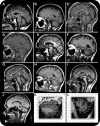

Results: The reported age at onset range was 39-71 years, and symptom duration was 3-38 years. The syndrome was identified in one sibling pair, suggesting that this may be a late-onset recessive disorder, although the other 16 cases were apparently sporadic. All 18 had sensory neuropathy with absent sensory nerve action potentials, although this was not apparent clinically in 2, and the presence of neuropathy was not a selection criterion. In 5, the loss of pinprick sensation was virtually global, mimicking a neuronopathy. However, findings in the other 11 with clinically manifest neuropathy suggested a length-dependent neuropathy. MRI scans showed cerebellar atrophy in 16, involving anterior and dorsal vermis, and hemispheric crus I, while 2 were normal. The inferior vermis and brainstem were spared.

Conclusions: Sensory neuropathy is an integral component of this syndrome. It may result in severe sensory loss, which contributes significantly to the disability. The MRI changes are nonspecific, but, coupled with loss of sensory nerve action potentials, may aid diagnosis. We propose a new name for the condition: cerebellar ataxia with neuropathy and bilateral vestibular areflexia syndrome (CANVAS).